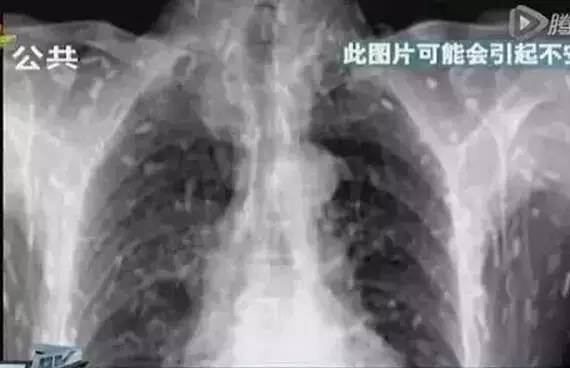

湖南一位孩子住院后,發現肺部有很大的陰影。原來,由于經常吃不熟的食物,他的肺里長滿寄生蟲,已經被「蟲子」吃出了兩個洞▼